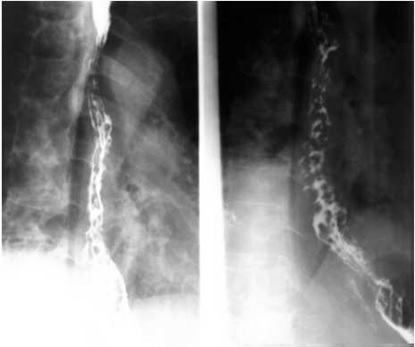

05卷-5.男性,胸骨后隱痛一年,請選擇正確答案(本題滿分2.00分)

本題答案:B

【該題針對“ 造影-食管靜脈曲張 ”知識(shí)點(diǎn)進(jìn)行考核】